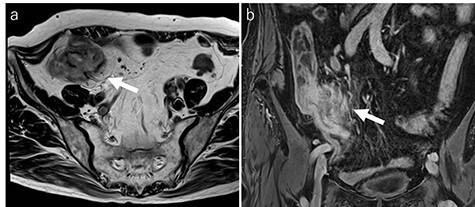

Xanthogranulomatous inflammation is an uncommon chronic inflammatory disease that develops most often in the kidneys and gallbladder. However, xanthogranulomatous appendicitis 45eXA is rare. Herein, we present a case of XA, with an elevated tumor marker, misdiagnosed as cecal cancer. A 76-year-old woman was referred to our hospital. Carbohydrate antigen 19-9 (CA 19-9) levels were elevated. By computed tomography and magnetic resonance imaging, we diagnosed as suspected cecal cancer and performed laparoscopic-assisted ileocecal resection. The pathological diagnosis was XA. Her CA19-9 level decreased to within normal limits. XA is a condition that results from an unusual healing pattern of appendicitis. However, the underlying mechanisms are still unclear. This is the first case of XA with elevated CA 19-9 levels. In this case, XA may have had the potential for malignancy. Our case report can aid in the understanding of these rare cases and, as a result, improve their prognosis.

黄色肉芽肿性炎症是一种罕见的慢性炎症性疾病,最常发生于肾脏和胆囊。然而,黄色肉芽肿性阑尾炎(XA)却很罕见。在此,我们报告一例XA病例,该病例肿瘤标志物升高,曾被误诊为盲肠癌。一名76岁女性被转诊至我院。糖类抗原19-9(CA 19-9)水平升高。通过计算机断层扫描和磁共振成像,我们诊断为疑似盲肠癌,并进行了腹腔镜辅助回盲部切除术。病理诊断为XA。她的CA19-9水平降至正常范围内。XA是阑尾炎一种异常愈合模式导致的病症。然而,其潜在机制仍不清楚。这是首例CA 19-9水平升高的XA病例。在本病例中,XA可能具有恶变潜能。我们的病例报告有助于了解这些罕见病例,从而改善其预后。